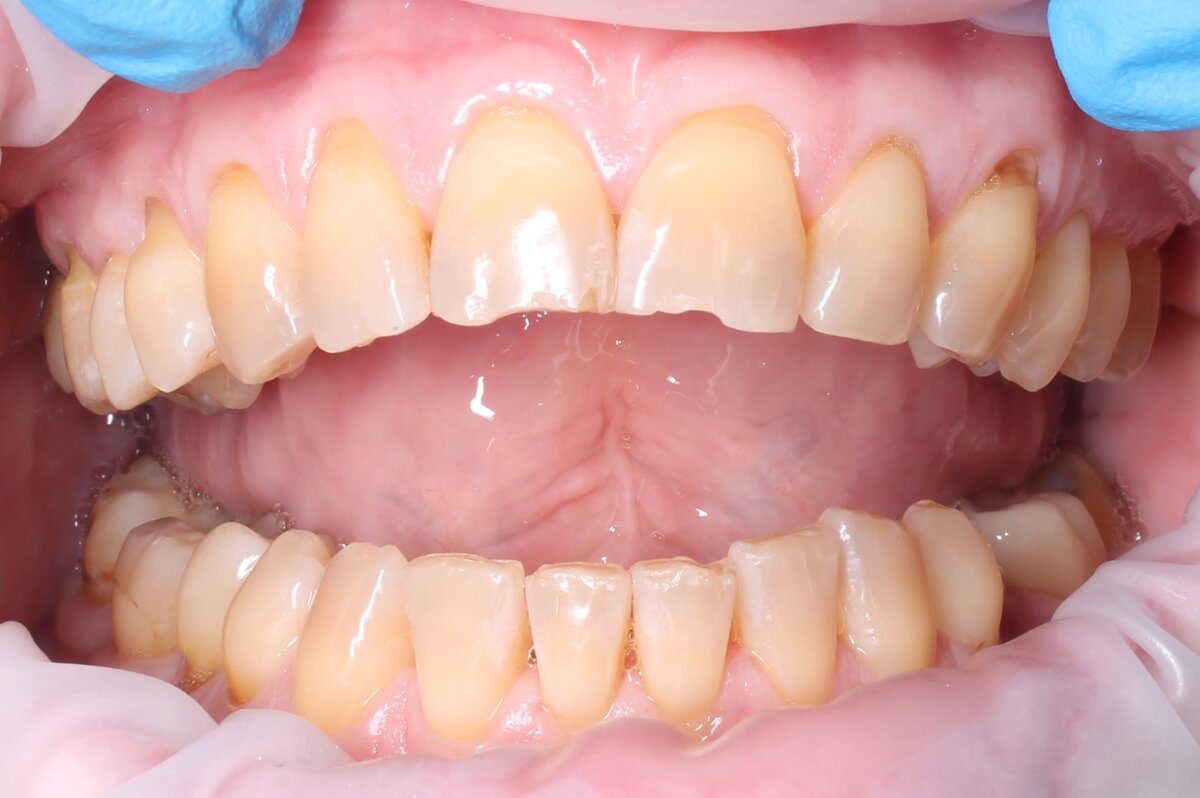

Невооруженным глазом видны рецесси десны (оголение корней).

Пациентка планирует установку виниров на верхние фронтальные 5 зубов. С ортопедом они приходят ко мне и просят подсобить в этом хорошем деле.

Но расширяю зону своей работы. Решаем оперировать всю челюсть в 2 этапа.